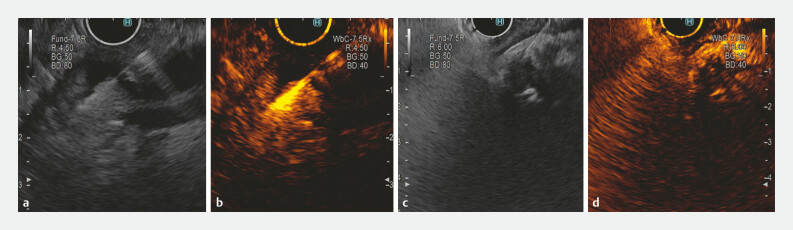

Results: Sixty-one patients were included in the study, 31 in the EUS-FNA group and 30 in the CH-EUS-FNA group. Mean age of participants was 74 ± 11.04 years and mean tumor size was 20.39 ± 9.17 mm, with 43 tumors in the distal bile duct. Final diagnoses were cholangiocarcinoma (37 cases), pancreatic ductal carcinoma (12 cases), other malignancies (3 cases), and benign lesion (9 cases). Diagnostic sensitivity, specificity, and accuracy were 83.3%, 100%, and 87.1% for EUS-FNA, and 82.1%, 100%, and 83.3% for CH-EUS-FNA. Plastic biliary stent placement and tumor location did not influence results. Hyperenhancement in the CH-EUS with rapid washout was observed in 90.9% of cholangiocarcinoma cases.

Abstract Image